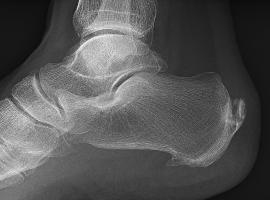

Citation: Ivana Topalovic, Dragana Matanovic, et al. Effects of the Shock Wave Therapy Application in Treatment of Heel Thorn: Calcar Calcanei. Clin Image Case Rep J. 2020; 2(2): 115.